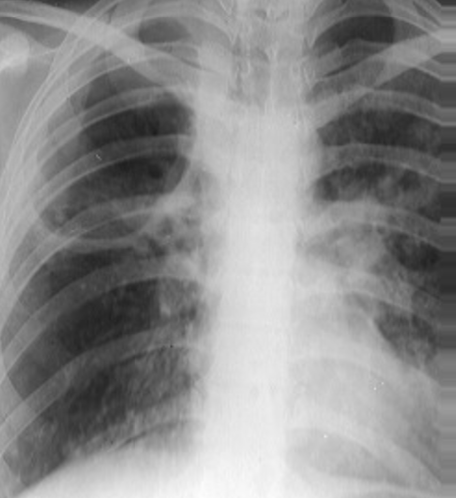

Rx toracică, incidență P-A

DESCRIERE:

DX: emfizem pulmonar

DD: